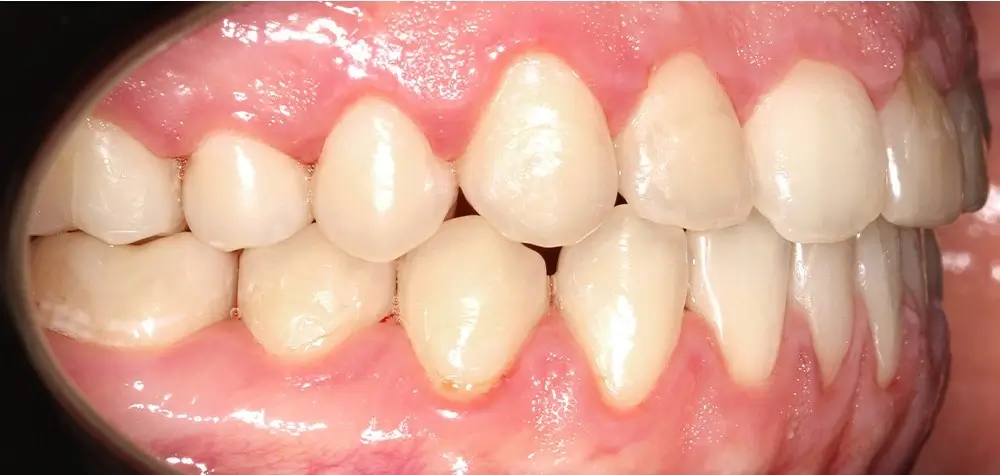

Открытый прикус - Кейс 4

Эффективность устранения дефекта прикуса посредством элайнеров FlexiLigner.

25

Количество кап НЧ

Количество кап ВЧ

Результаты лечения